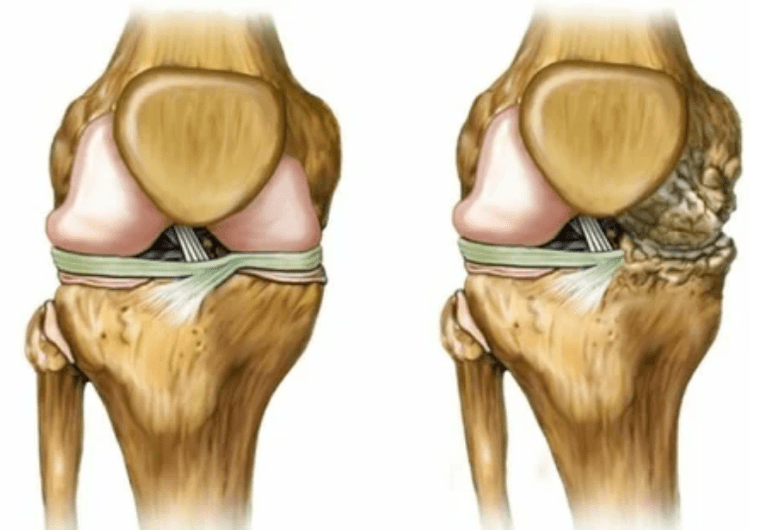

- 1 grado. I disturbi morfologici sono già iniziati, ma non sono ancora sorprendenti. La patologia influenza principalmente la condizione del fluido sinoviale, che fornisce tessuto di cartilagine più scarso con componenti nutrizionali e riduce la forza della cartilagine. Lo stress sulle articolazioni porta a infiammazione e dolore.

- Livello 2. A causa della mancanza di pensione, le cartucce necessarie vengono distrutte. La crescita ossea si forma sulla superficie della cartilagine. Il dolore ha acquisito un carattere più pronunciato, si rafforza dopo una lunga pausa e sono eliminati da piccoli lavori fisici. Il dolore è accompagnato da infiammazione. I muscoli sono allungati, il che porta a menomazioni deboli o medie delle funzioni motorie.

- 3 gradi. C'è spesso dolore, è difficile spostare l'arto a causa dei cambiamenti nell'articolazione. Le lesioni sono estese e sono evidenti per il look nudo. La deformazione della posizione articolare si verifica, l'area interessata si gonfia e diventa rossa. L'asse dell'arto è disturbato, il che porta alla complessità del movimento. I legamenti producono cambiamenti patologici. Appaiono subbluish e contratture. I muscoli adiacenti vengono accorciati o allungati da cui la funzione contrattile è indebolita.